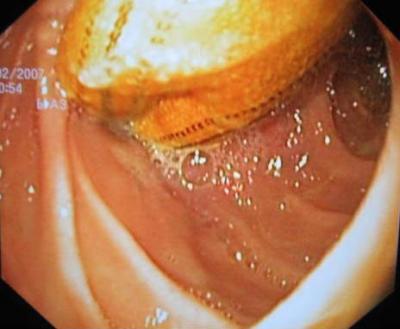

Aorto-duodenal fistulae (ADF) are the most frequent aorto-enteric fistulae (80%) and the most frequent presenting sign of ADF is upper gastrointestinal bleeding (UGI). A 59-year-old male patient, who underwent an aortic-bi-femoral bypass five years ago, was admitted to the Emergency Room after five days of persistent occlusive syndrome with dyspepsia and biliary vomiting. Computed tomography (CT) scan showed in the third duodenal segment the presence of an area with the characteristics of inflammatory tissue, including air bubbles between the duodenum and aortic-bi-femoral prosthesis adherent to the third duodenal portion (¡°comma sign¡±) (Figure 1). Microbiological cultures and scintigraphy were unremarkable. Esophago-gastro-duodenoscopy showed the aortic prosthesis crossing the third segment of duodenal wall occluding the intestinal lumen (Figure 2). At laparotomy, after viscerolisis, the prosthesis was detached from duodenal wall and the intestine failed to close transversely (Figure 3). To protect the intestinal wall, a pediculated fragment of the greater omentum was placed between the duodenum and aortic bypass. Furthermore, a gastrojejunal Roux anastomosis was employed. The prosthesis was not changed because there were no local or systemic signs of infection. The post-operative course was uneventful.